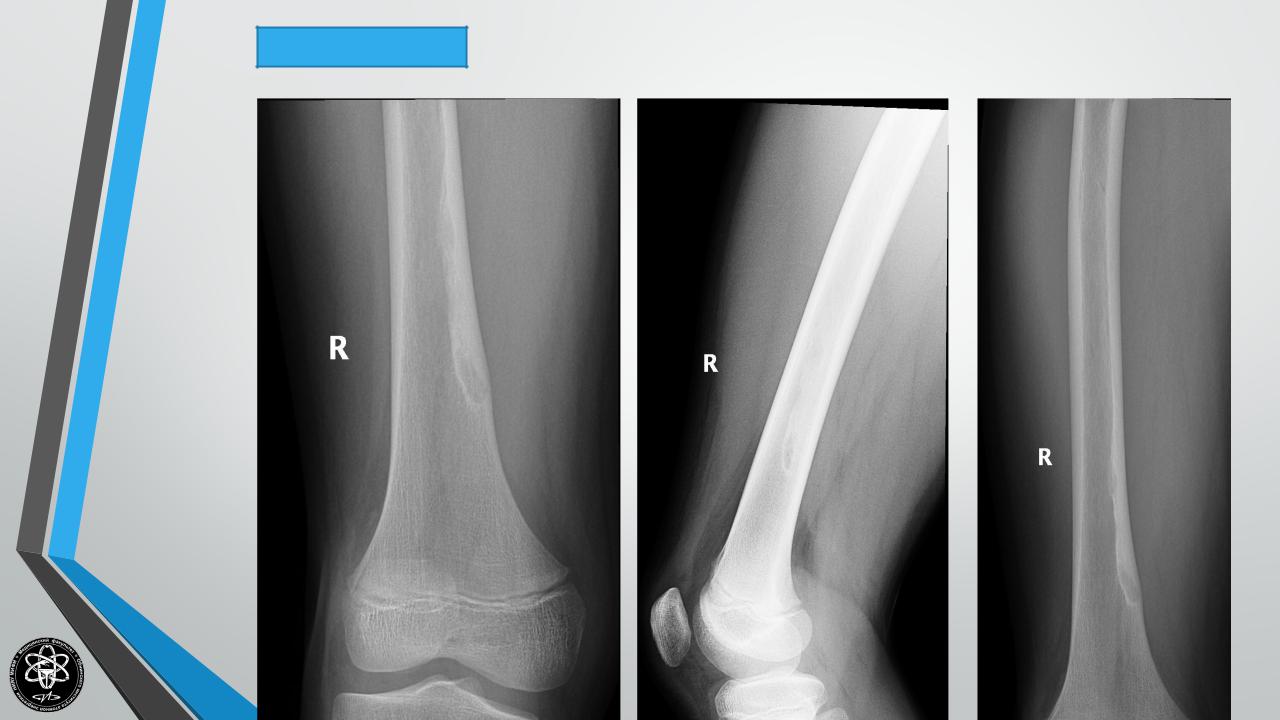

ОСТЕОИД-ОСТЕОМА

Частота — 4 % всех опухолей скелета.

Поражаемый возраст — 20-30 лет.

Излюбленная локализация — большеберцовая и малоберцовая кости, но может локализоваться в локтевом отростке и др. костях.

Клиника — выраженный болевой компонент. Иногда боли носят мучительный характер. Выраженное нарушение функции.

Рентгенологическая картина — зона просветления, окруженная ободком склероза, в центре часто секвестр.

Гистологически — полость, выстланная грануляционной тканью, в центре — секвестр, достигающий величины горошины.

Лечение хирургическое — краевая резекция кости в пределах здоровой ткани.

Исход — выздоровление. Рецидивы редки. Озлокачествления не наблюдается.